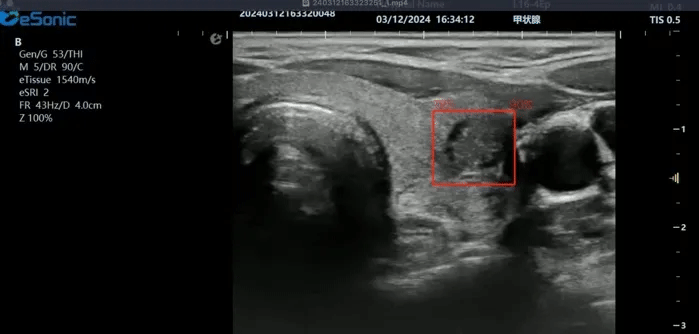

新航娱乐医疗(ESI)表示,其最新的人工智能功能可以帮助到医疗机构的工作效率,功能包括,实时、动态、快速自动识别病灶,良恶性病灶概率预测,甲状腺结节和乳腺的二维灰阶动态自动实时检测需求,提供多个结节动态检测轮廓框。实时获取多幅具备临床特征(大小、属性等)的结节切面,同时提供当前切面所示结节的结节大小、属性特征、TI-RADS 分级。

对于甲状腺结节相关的自动检测功能,甲状腺结节病灶检出率≥95%,良恶性分类灵敏度≥90%、良恶性分类特异度≥85%。